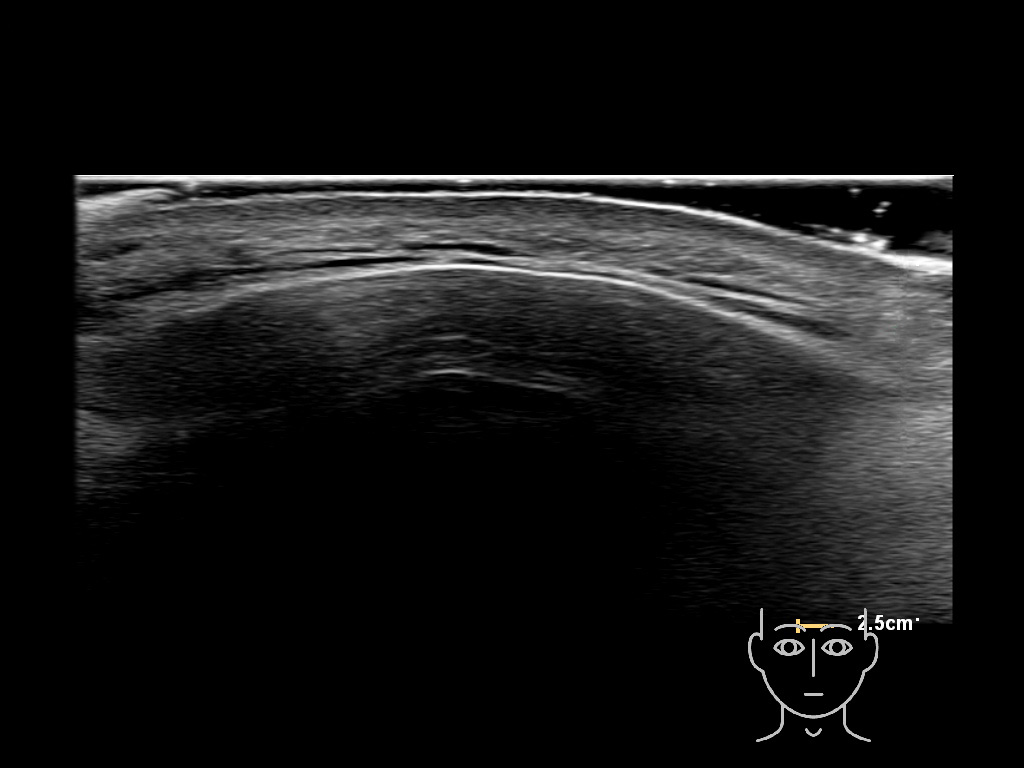

In this section you will learn more about the different layers of the face with the use of ultrasound. When you click on the secondary ultrasound image, you will see the different structures as an overlay. This will help to train yourself to recognize the different layers of the face.

Study the first image to recognize the different layers. If you are sure about the layers, swipe to the second image to view the answer (if applicable).